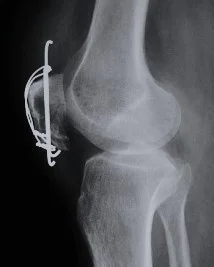

| Tension Band Wires | Special mechanics in – Patella – Olecranon – Malleolar fractures | ![]() |